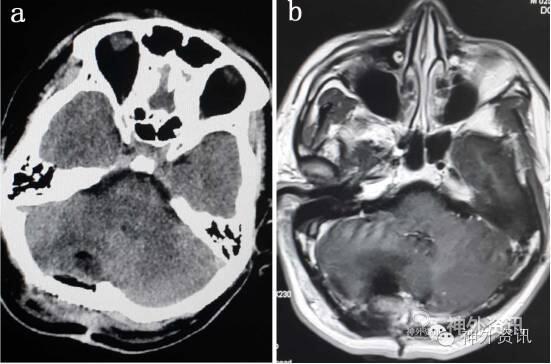

术后患者头痛好转。CT检查无残腔出血等。

MRI示:小脑复发肿瘤术后改变,右侧小脑半球可见异常信号灶,呈长T1长T2信号,周边可见条状短T1信号,附近可见脑组织水肿,增强后未见强化(图5)。

图5. 术后CT及MRI显示,术后改变,无残腔出血,周边有水肿。